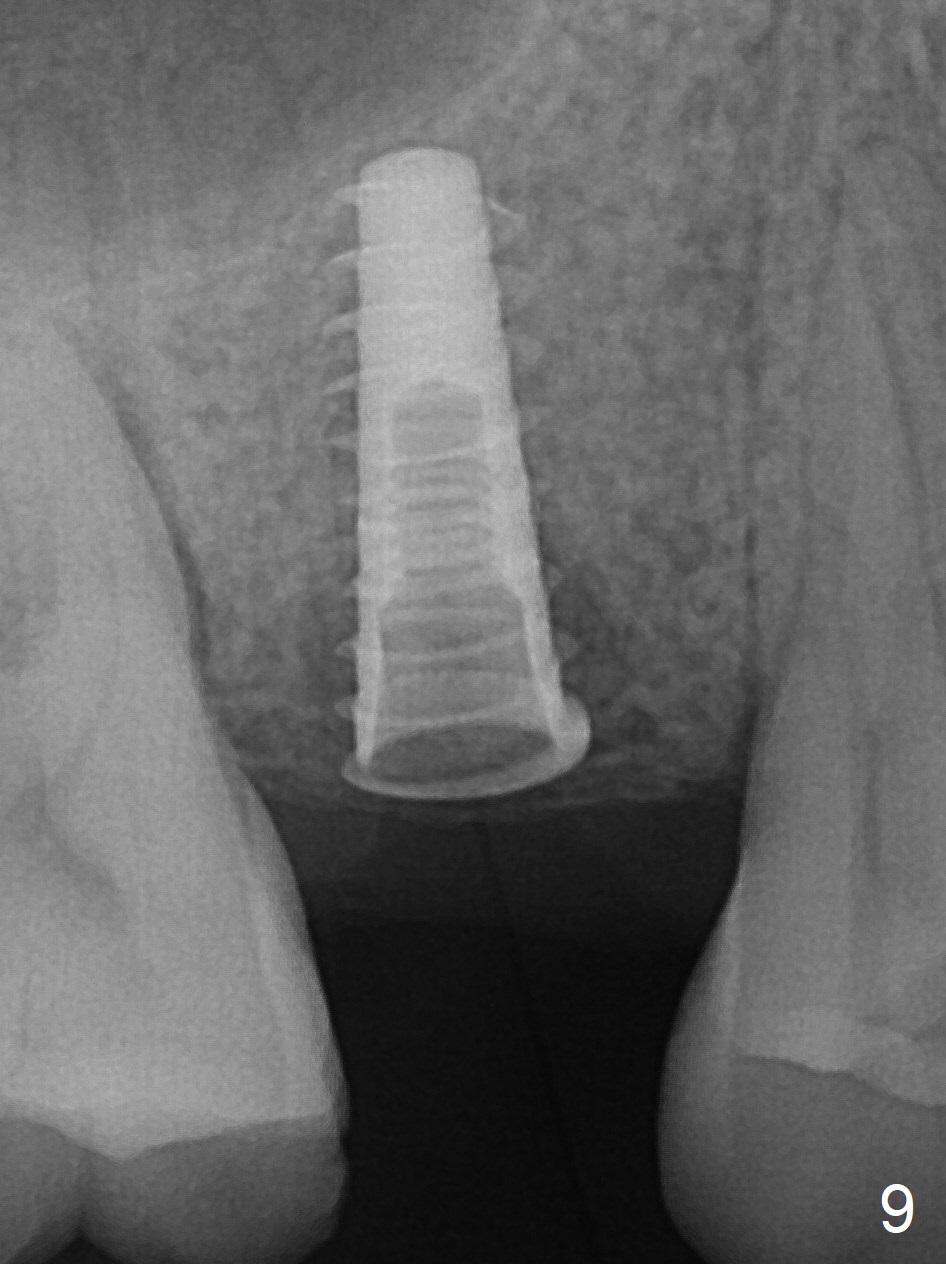

The implant dislodges while the abutment is untightened 8 months postop. The osteotomy is found intact. A 4.5x11 mm dummy implant is placed 2 mm subgingival with 20 Ncm (Fig.9). When a 4.5x11 mm definitive implant is placed 3 mm subgingival (Fig.10,11), torque reaches 50 Ncm. A 5.5x3 mm healing abutment is placed.